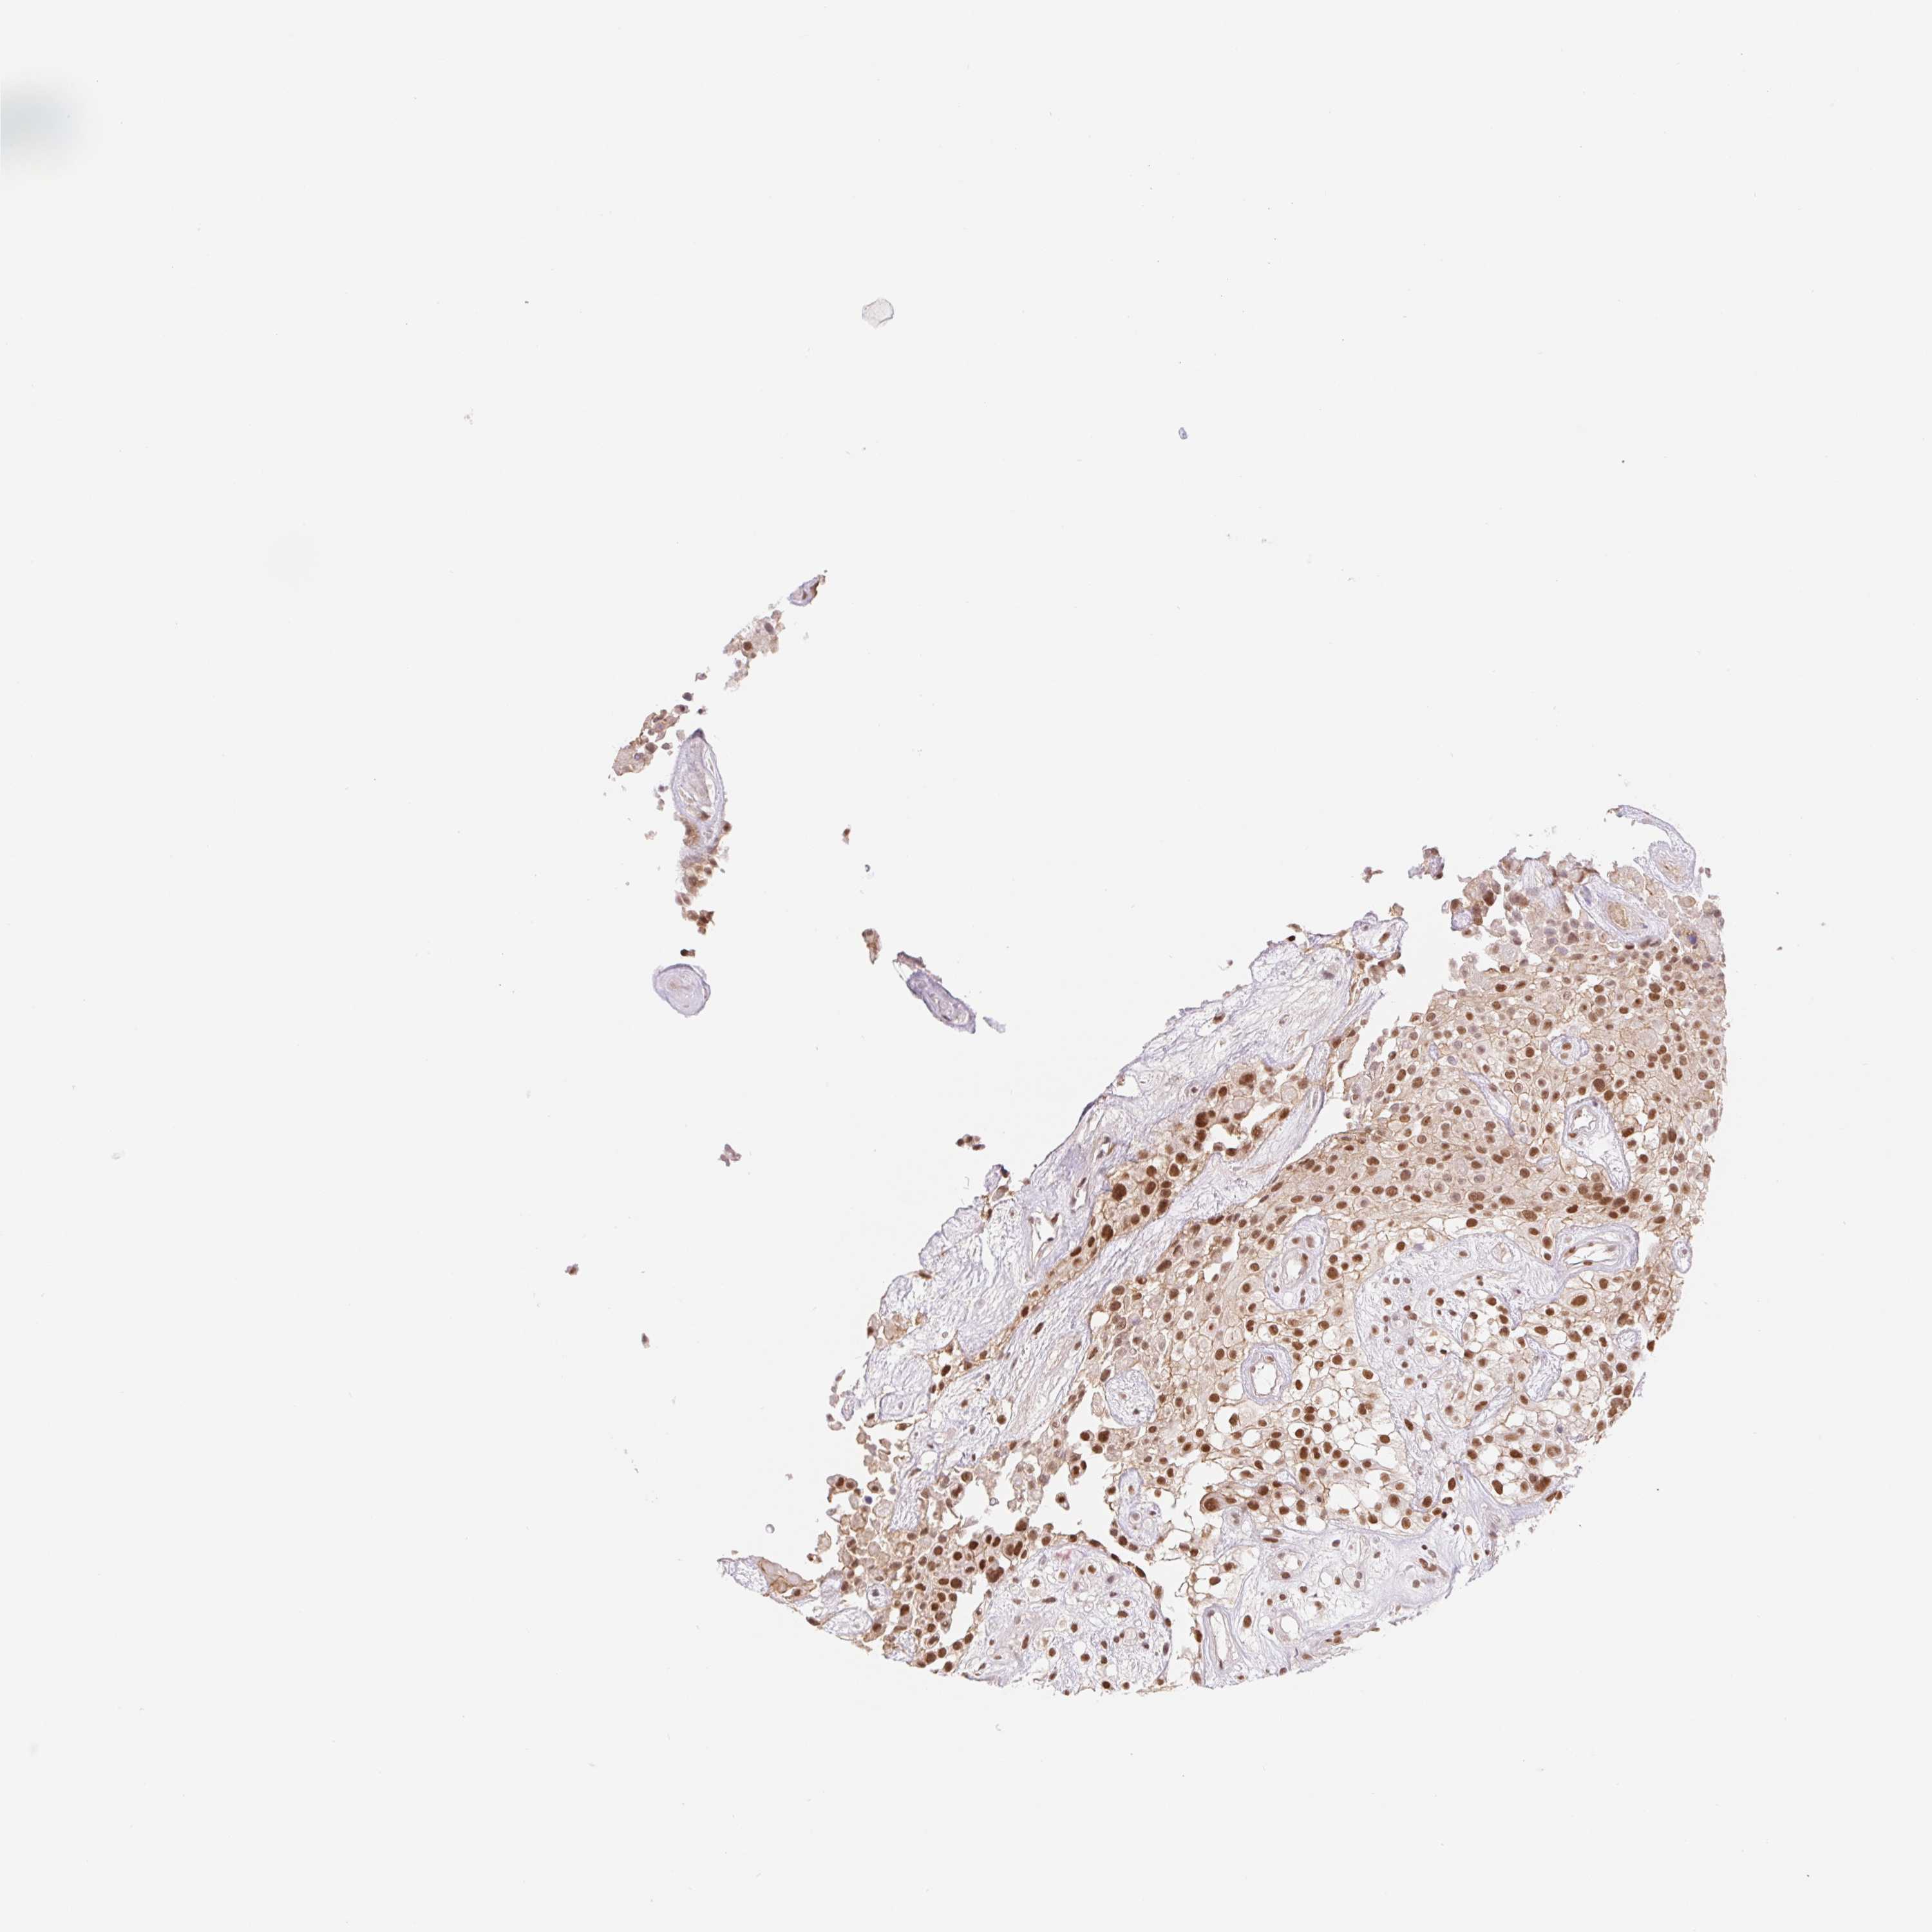

UROTHELIAL CANCER - Protein expressioni

A mouse-over function shows sample information and annotation data. Click on an image to view it in a full screen mode. Samples can be filtered based on level of antibody staining by selecting one or several of the following categories: high, medium, low and not detected. The assay and annotation is described here.

Note that samples used for immunohistochemistry by the Human Protein Atlas do not correspond to samples in the TCGA dataset.

Antibody stainingi

Antibody staining in the annotated cell types in the current human tissue is reported as not detected, low, medium, or high, based on conventional immunohistochemistry profiling in selected tissues. This score is based on the combination of the staining intensity and fraction of stained cells.

Each image is clickable and will lead to virtual microscopy that enables deeper exploration of all samples and also displays staining intensity scores, fraction scores and subcellular localization as well as patient and tissue information for each sample.

Antibody HPA059943

Staining

High

Medium

Low

Not detected

Intensity

Strong

Moderate

Weak

Negative

Quantity

>75%

75%-25%

<25%

None

Location

Nuclear

Cytoplasmic/membranous

Cytoplasmic/membranous,nuclear

Urothelial carcinoma, High grade

Urothelial carcinoma, NOS

Urothelial carcinoma, Low grade